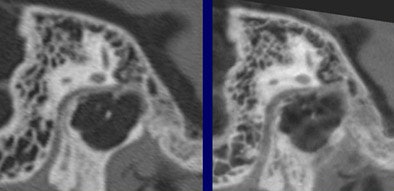

| The flat-panel VCT images of the skull base at right were rated significantly higher in image quality compared to 16-slice MDCT images of the same regions at left, by two readers rating 21 features independently. Images (from top to bottom) include stapes and ovale window niche (above), facial nerve canal (below), maxillofacial region, and implanted microscrews (bottom). All images courtesy of Dr. Sönke Bartling. |

"The same holds true for small and especially thin structures within the maxillofacial region, for example the medial limitation of the orbital cavity is much better delineated in flat-panel-based volume CT," Bartling said. And the technique produces fewer metal artifacts, he added.